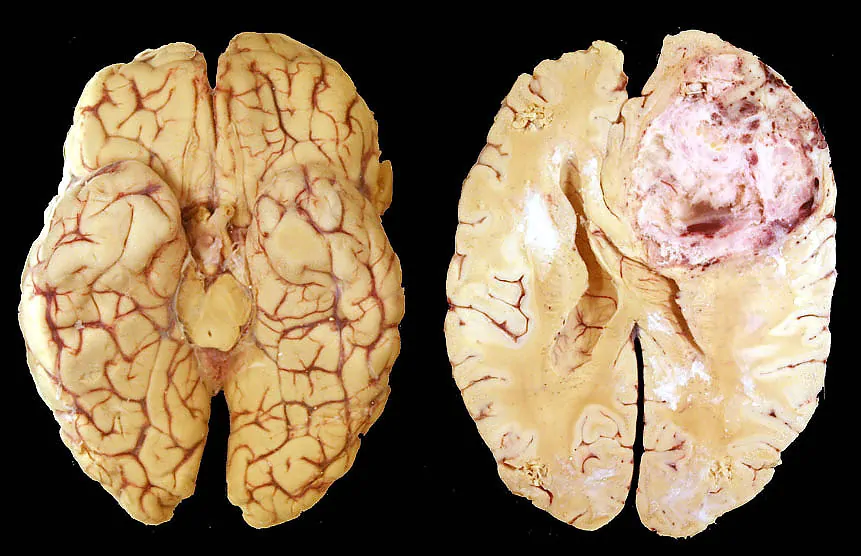

Il glioblastoma multiforme è il tumore cerebrale primario più comune, rappresentando il 54% di tutti i gliomi e il 15% di tutti i tumori cerebrali primari negli adulti. Si tratta di una neoplasia letale, con una sopravvivenza mediana di soli 15 mesi dalla diagnosi. La ricerca ha mostrato risultati promettenti, in particolare per quanto riguarda l’uso delle nanoparticelle, che hanno dimostrato di essere biocompatibili e di avere un effetto sinergico se combinati con il trattamento chemioterapico.